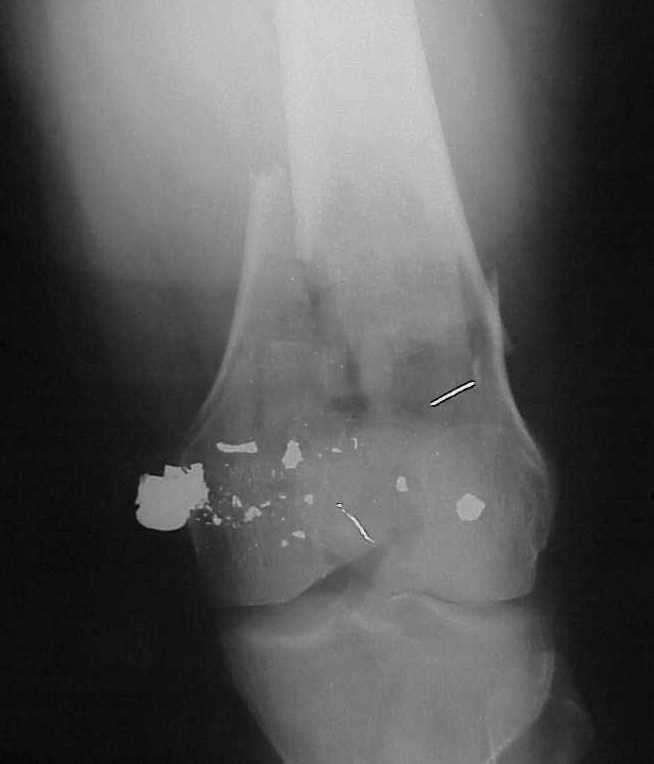

Use 6.5 mm cannulated screws if you have and

place one anterior to where IMN will go if anterior cortex if insufficient and AP screws on either side of the IMN out of the trochlea to provide some additional varus/valgus stability. I worry about the leg going into valgus w/the lack of lateral cortex.

See attached case that was done several years ago before LISS. He had comminuted trochlea and anterior blocking screws were used to prevent anterior IMN cut-out.